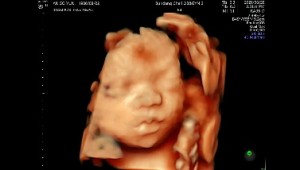

26w6d [너에게 쓰는 편지]

띵동아 너가 우리에게 와준지 벌써 약 27주라는 시간이 되었어. 난 아직 엄마라는 단어가 낯설지만 몸과 마음이 힘들 때 너의 움직임에 가슴이 떨리고 모든게 괜찮아질 때 그럴 때 마다 내가 엄마가 맞구나 싶어. 이제 두달 반 가량 뒤면 너가 이 세상에 나올텐데 그 때 까지 내 뱃속에서 잘 놀고 있어. 그리고 건강해야해. 어린 엄마지만 너에게 만큼은 큰 어른이고싶어. 너에게 좋은 친구같은 엄마가 될 수 있도록 항상 노력할게. 21년 살았지만 너를 품은 27주 이 짧은 시간이 내 인생에서 가장 소중하고 가장 행복한 시간이야. 입덧때문에 모든게 싫고 숨 쉬는 것 조차 힘들다고 버겁다고 느낄 때도 초음파보고 너가 건강하단 사실을 알고 안도의 눈물을 얼마나 흘렸는지 몰라. 넌 그런 존재야. 세상에 무너진다해도 난 너를 지킬게 사랑해 아가야? 그리고 내 아들이 되어주어서 고마워